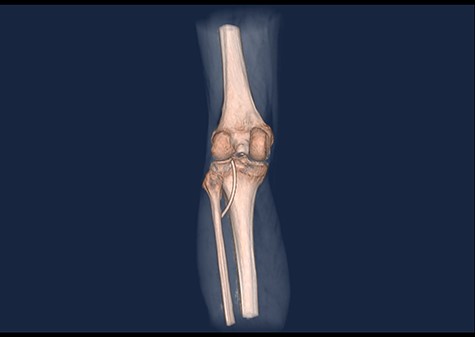

3D CT scan showing posteroanterior view with catheter embolus in the level of the left knee.